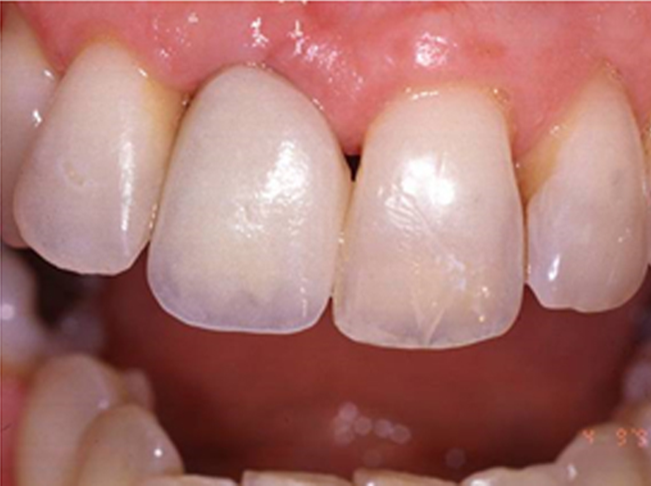

Enhanced Aesthetics: Achieve a radiant smile while preserving jaw health.

Comprehensive Restoration: Natural appearance, full function, and lifetime reliability.

Stability and Confidence: Enjoy unrestricted bite function with lifelong comfort.

• Natural Look, Feel, and Function: Implants restore the appearance, feel, and functionality of natural teeth.

“The QDC Dental Implants”

look and feel like your very natural teeth designed to be fixed for lifetime.